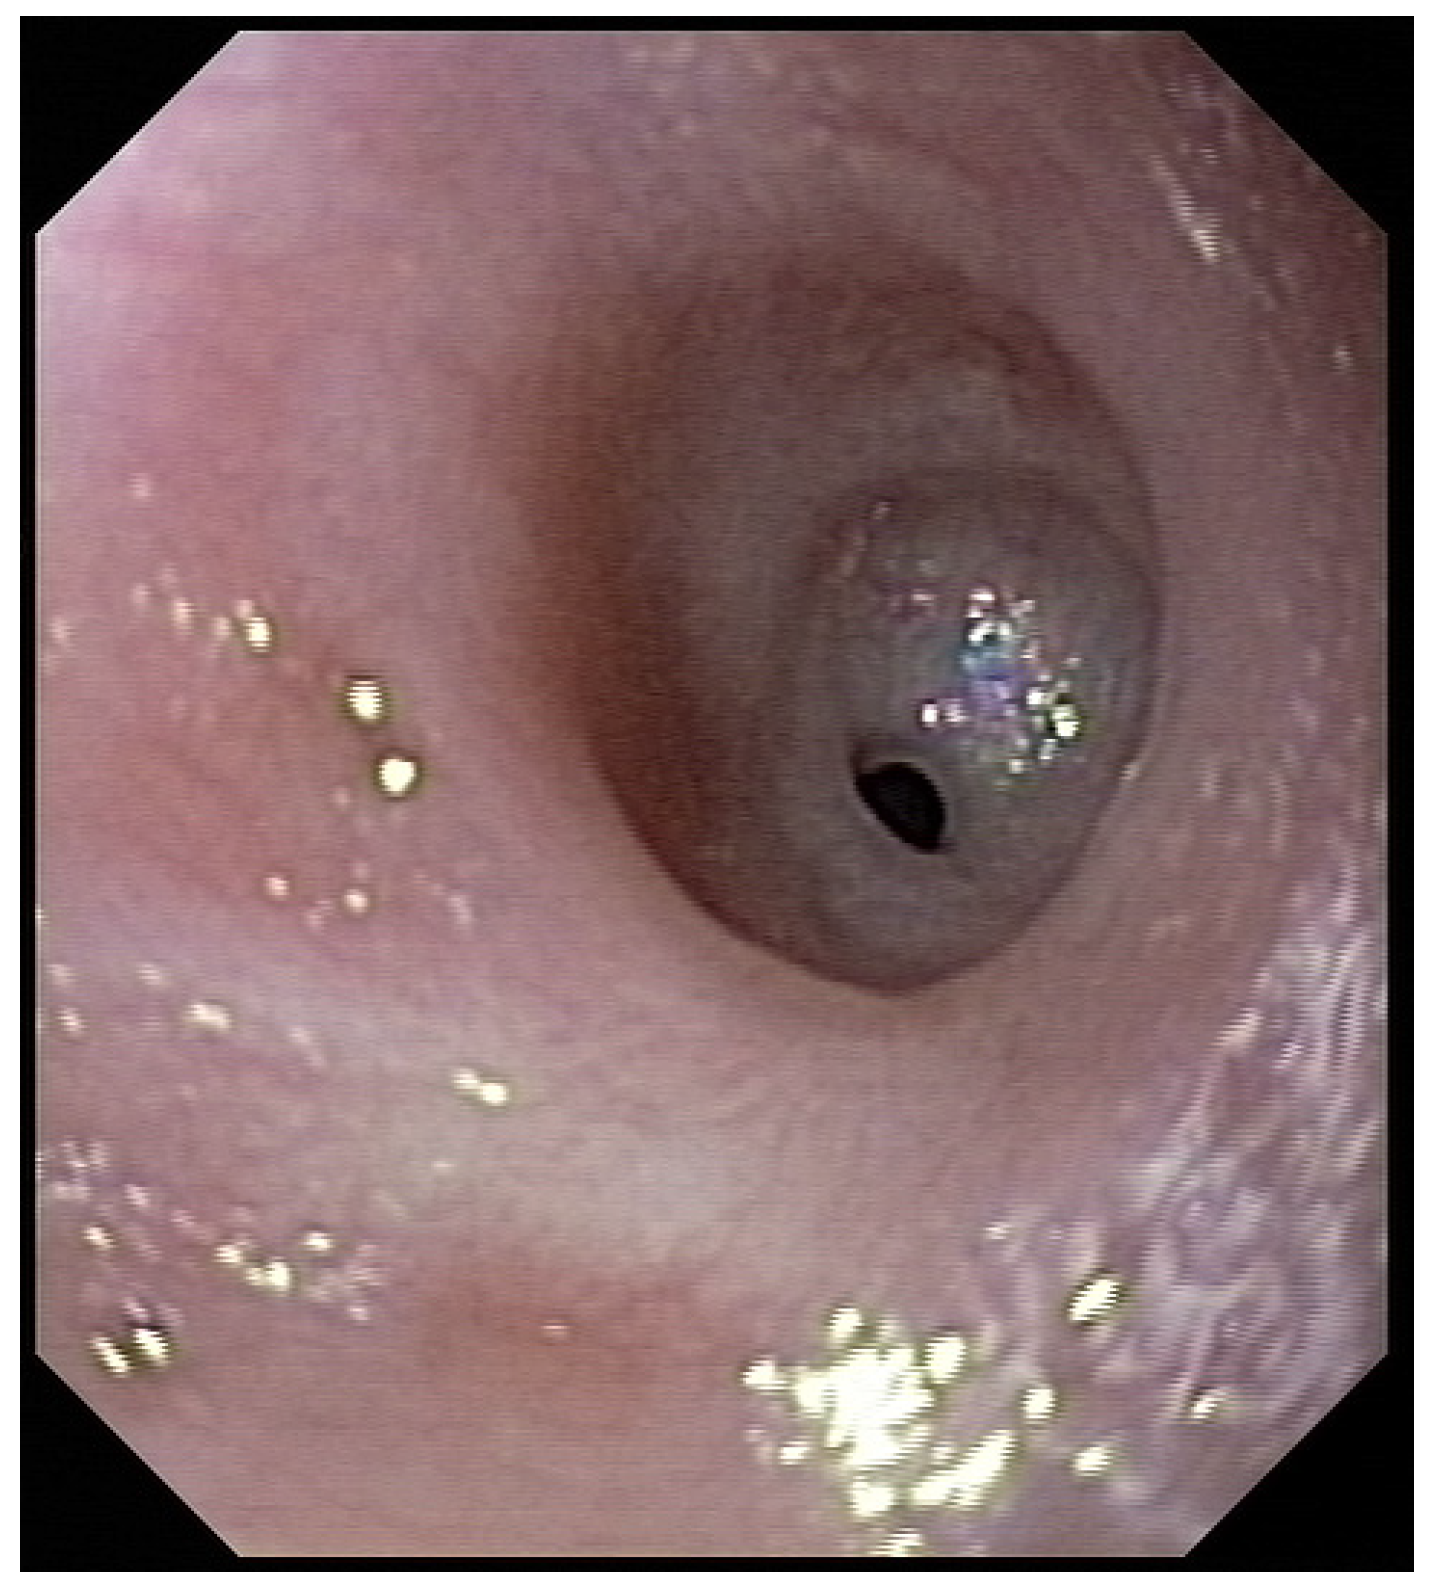

Three weeks before surgery, the children were transferred from Africa to Switzerland for the evaluation of their nutrition status, as they eventually needed to be fed carefully and progressively. A thoracic X-ray and an esophagogram are performed (

Figure 2). Intubation allowed an endoscopic evaluation of the grade of esophageal and pharyngeal stenosis and mobility of the vocal cords (

Figure 3). This evaluation was done with our ear nose and throat (ENT) colleagues, and eventual tracheotomy was discussed for very high stenosis of the larynx without residual damage to the esophagus.